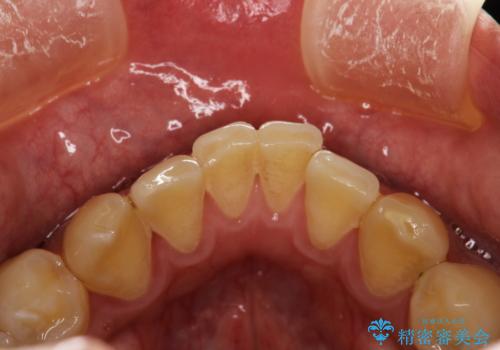

プラーク(細菌の塊)や歯石がたまると歯の表面はザラつきいてきます。そのザラつきは歯周病や虫歯菌の棲家となります。そのまま放置すると、歯肉が腫れてきたり、歯肉から出血したり、口臭が強くでたりします。とくに歯肉の境目は、歯磨きで汚れを除去することが難しく、プラーク(細菌の塊)や歯石が溜まりやすい場所です。

歯並が、がたついている場合はなおさら汚れが溜まりやすいです。矯正治療前や定期的にPMTCをすることで、歯肉トラブルを防ぐことにつながります。